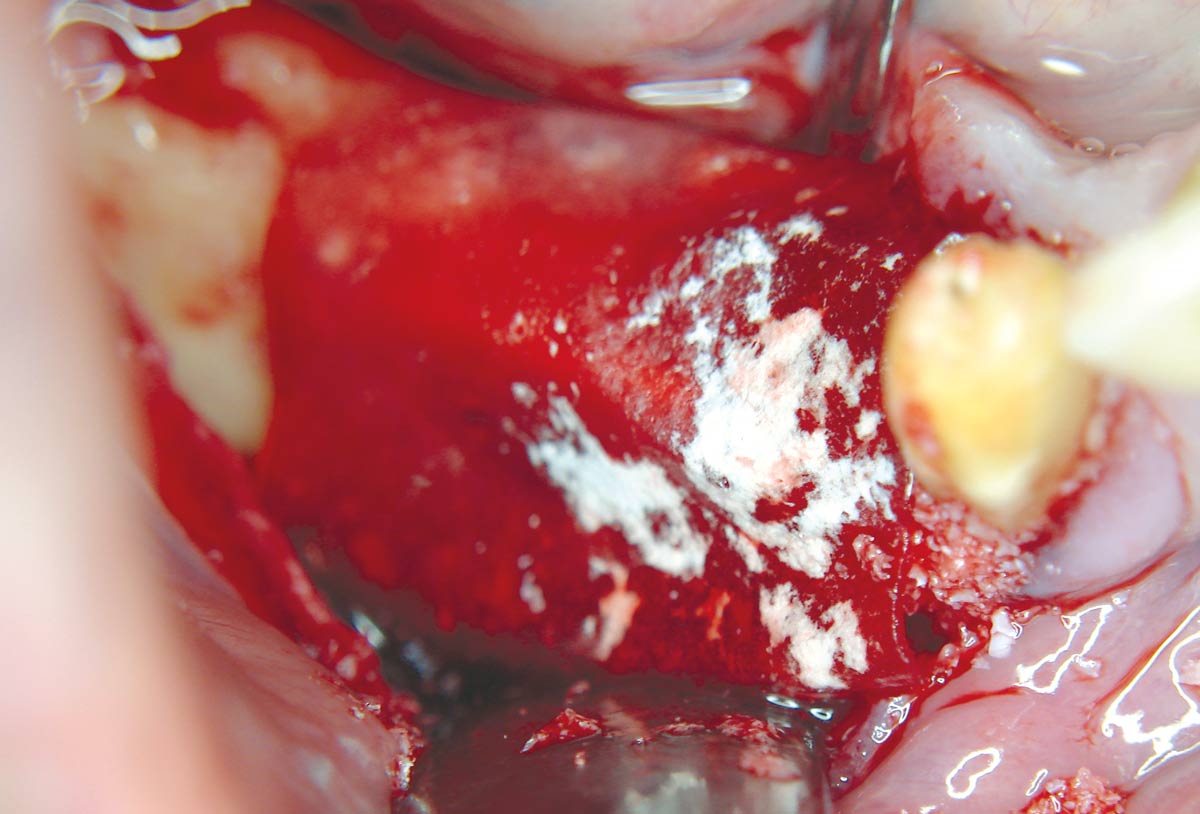

05 / 20 - Defect-filling and contouring with cancellous allogenic bone chipsHorizontal ridge augmentation with maxgraft® cortico - M.Sc. E. Kapogianni